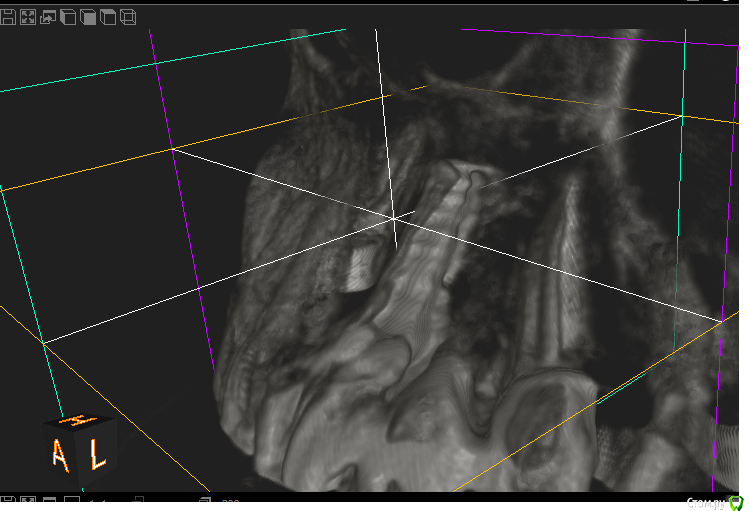

ikaZonter Опубликовано 27 апреля, 2016 Поделиться Опубликовано 27 апреля, 2016 Здравствуйте уважаемые коллеги! Год назад пациентке был установлен имплант в поз 21.на контрольном осмотре ч\з 9 мес , имплант подвижен. на кт вестиб. стенка ушла полностью.Посоветуйте как поступить в плане восстановления, блок или графт+ каркасная мембрана? во сколько этапов?Заранее всем спасибо! Ссылка на комментарий

ikaZonter Опубликовано 28 апреля, 2016 Автор Поделиться Опубликовано 28 апреля, 2016 хочет сохранить имплант сохранить ? даже не думал об этом. Имплант убирать однозначно, вопрос в том как поступить дальше?! вестибулярки неивидно не от того что фонит металл ? к сожалению не фонит .((( Ссылка на комментарий